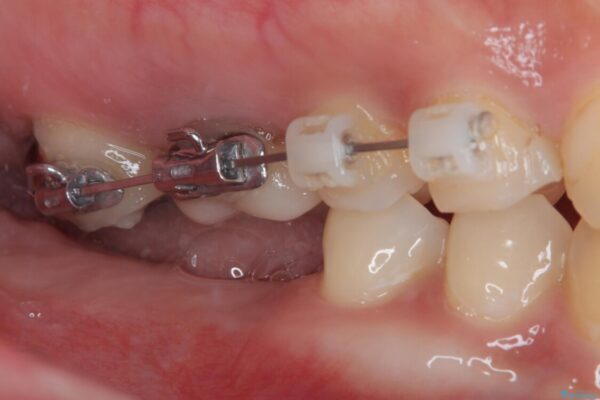

そこで、右上の奥歯に部分的なワイヤーを装着し、さらに矯正用アンカースクリュー(TADs)を併用することで、挺出した歯を圧下(歯を元の高さに戻す動き)させ、下顎にインプラントを埋入するための十分な垂直的スペースを確保しました。

→ この装置は部分的な矯正で、前歯など見える位置にワイヤーがかかることはなく、見た目を気にすることなく、普段通りの生活を送りながら治療を進めることができました。

治療途中

• 挺出歯を圧下してスペースを確保!目立たない部分矯正で下顎大臼歯にインプラント治療を実現 治療途中画像